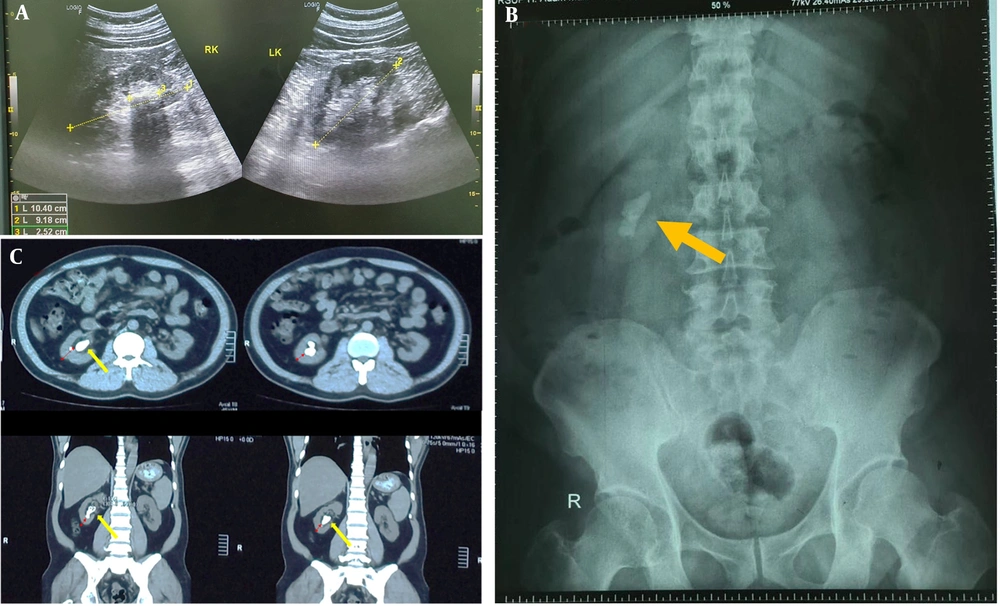

Abdominal ultrasonography showed a stone mass with an acoustic shadow in the right kidney (Figure 1A). This was followed by a kidney, ureter, and bladder (KUB) X-ray, which revealed a 3-centimeter right renal stone (Figure 1B). Subsequently, an abdominal non-contrast computed tomography (CT) scan was performed for better visualization of the renal stones and surrounding organs. The CT scan showed a 3-centimeter right pelvicalyceal stone with a thick renal parenchyma (Figure 1C). The patient had not undergone any previous surgical interventions. After obtaining informed consent, we decided to perform laparoscopic nephrolithotomy due to the patient's condition.

A, an abodminal ultrasonography showed a hyperechoic mass with accoustic shadow in right kidney; B, a KUB X-ray showed a radio opaque stone mass in right kidney (yellow arrow); C, an abdominal CT scan showed 3 centimeters renal stones in right kidney (yellow arrow) with thick renal parenchyma (red arrow).